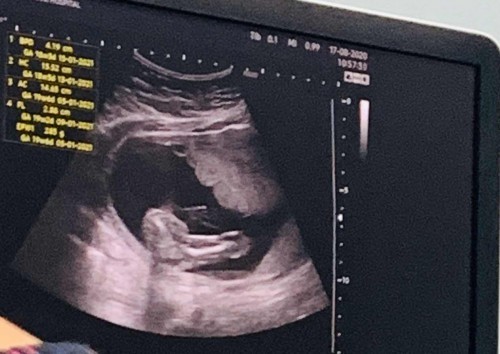

ผลตรวจ 19W

ผลอัลตร้าซาวด์ แบบนี้ ผู้หญิง ผู้ชาย แม่ๆช่วยดูหน่อยจ้า

ช มั้งคะ